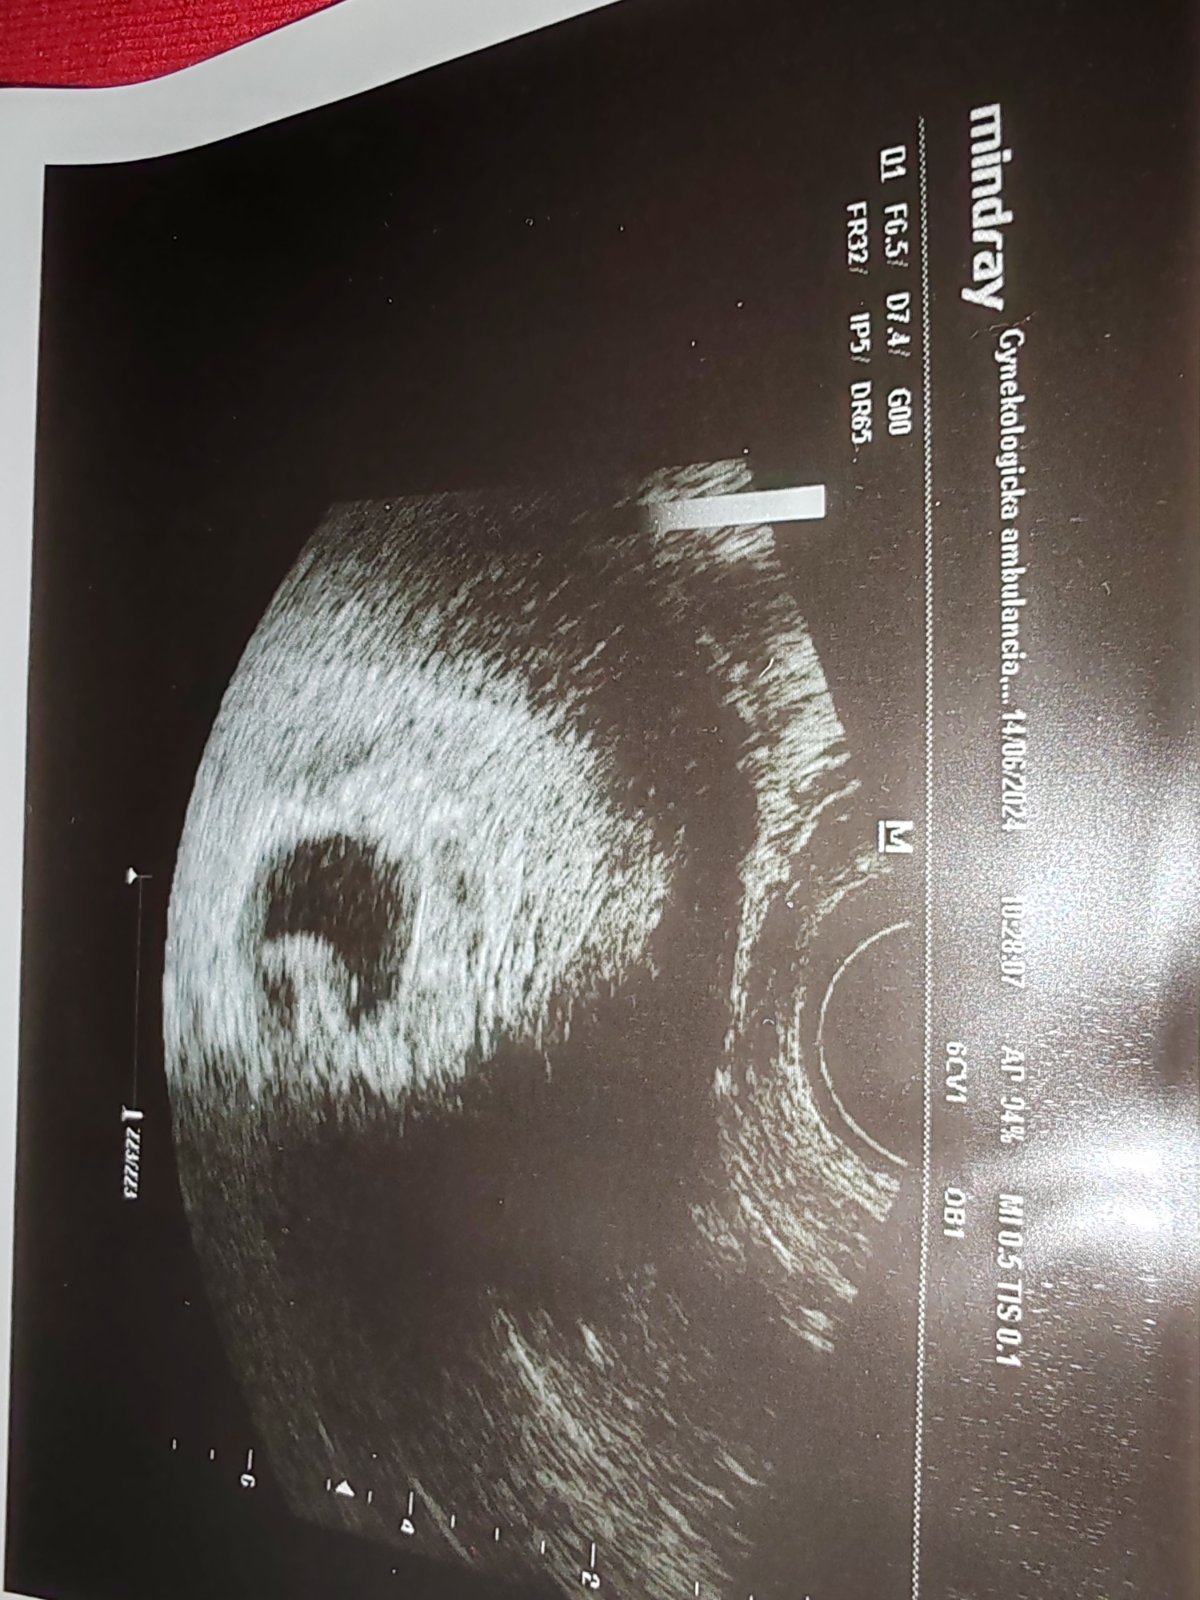

Vidíte na ultrazvuku dva plody?

@vevericaxxl tak este dalsie dva neiste tyzdne :/ v kazdom pripade je stastie ze je v maternici a nie niekde vo vajecniku zatulane. Druhe pozitivum je ze podla mna narastlo oproti poslednemu sonu. Minule mi vysvetlovala moja gyneko ze napriklad tu znacku sona co ma, tak uz existuje 20 generacia a ona ma napr. nejaku 10tu v ordinacii a ze dufa ze ked ju splati tak si bude moct kupit aspon 13ku. Kazdy novsi model je o nieco lepsi a preto niekde uz lekar vidi a niekde nie nieco na sone. Citis sa ako?

@vevericaxxl presne takto vyzeralo moje sono v 5tt. Ako v tvojom poslednom komentári. Respektíve asi v 6tt. Všetko bolo v poriadku, o dva týždne bolo už aj srdiečko a teraz máme.2,5r dcerku. Držím palce